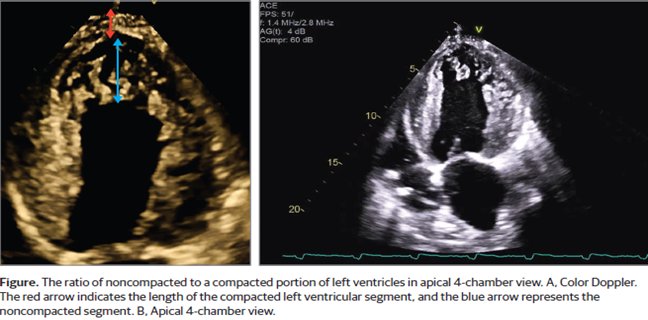

48- χρονος παρουσιάσθηκε στα ΤΕΠ με επιδεινούμενη δύσπνοια και εικόνα καρδιογενούς shock

Noncompaction αριστ κοιλίας . JAMA Cardiology August 2025 Volume 10, Number 8